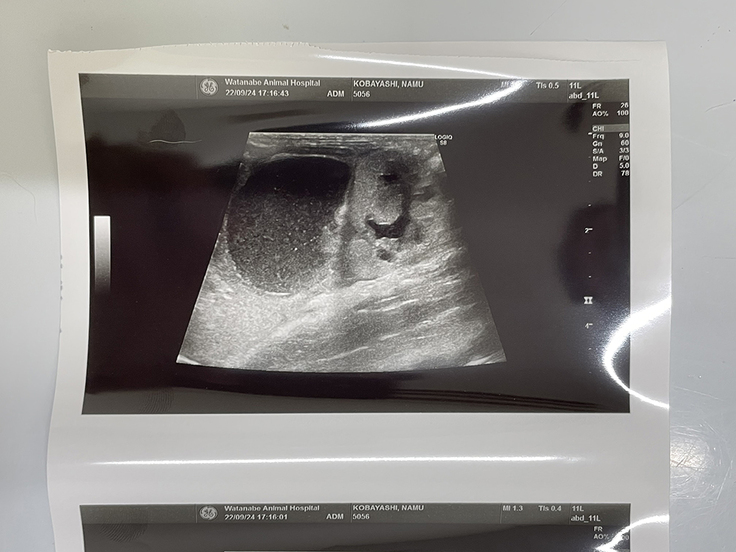

9月24日現在↑ 事故の影響で腹腔内に溜まっている腹水(黒い部分)のエコー

排尿の回数は少し多いが、排便は順調。